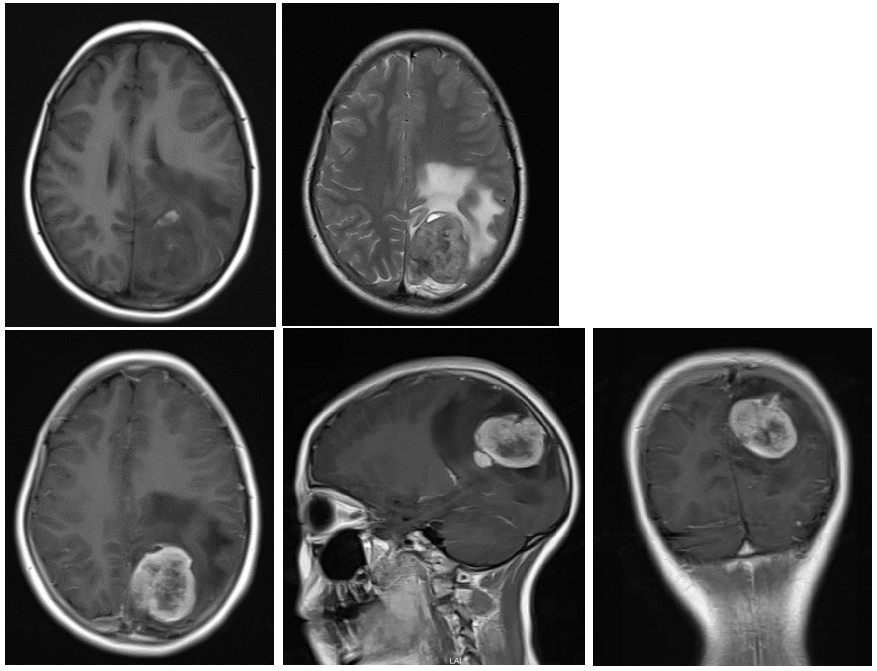

弥漫性星形细胞瘤(ii级)

例1 弥漫性星形细胞瘤